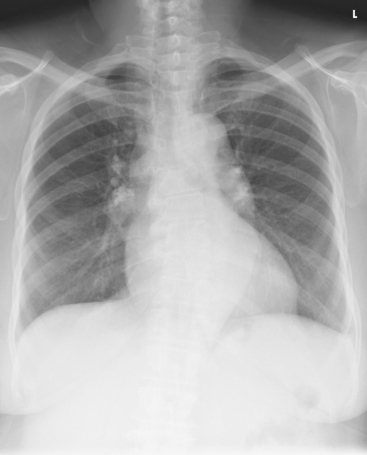

Structures shown: An AP projection of the thoracic viscera (Fig. 10-51) shows an image similar to the PA projection (Fig. 10-52). Being farther from the IR, the heart and great vessels are magnified and engorged, and the lung fields appear shorter because abdominal compression moves the diaphragm to a higher level. The clavicles are projected higher, and the ribs assume a more horizontal appearance.

For radiography of the heart and lungs, the patient is placed in an upright position whenever possible to prevent engorgement of the pulmonary vessels and to allow gravity to depress the diaphragm. Of equal importance, the upright position shows air and fluid levels. In the recumbent position, gravitational force causes the abdominal viscera and diaphragm to move superiorly; it compresses the thoracic viscera, which prevents full expansion of the lungs. Although the difference in diaphragm movement is not great in hyposthenic individuals, it is marked in hypersthenic individuals. Figs. 10-10 and 10-11 illustrate the effect of body position in the same patient. The left lateral chest position (Fig. 10-12) is most commonly employed because it places the heart closer to the IR, resulting in a less magnified heart image. Left and right lateral chest images are compared in Figs. 10-12 and 10-13.